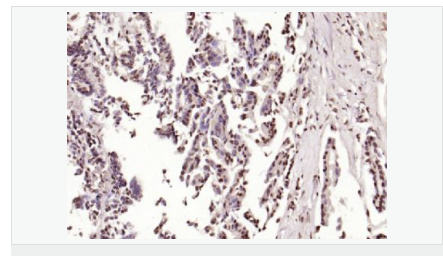

| 產(chǎn)品應用 | ELISA=1:5000-10000 IHC-P=1:100-500 IHC-F=1:100-500 Flow-Cyt=1μg/Test ICC=1:100 IF=1:100-500 (石蠟切片需做抗原修復) not yet tested in other applications. optimal dilutions/concentrations should be determined by the end user. |